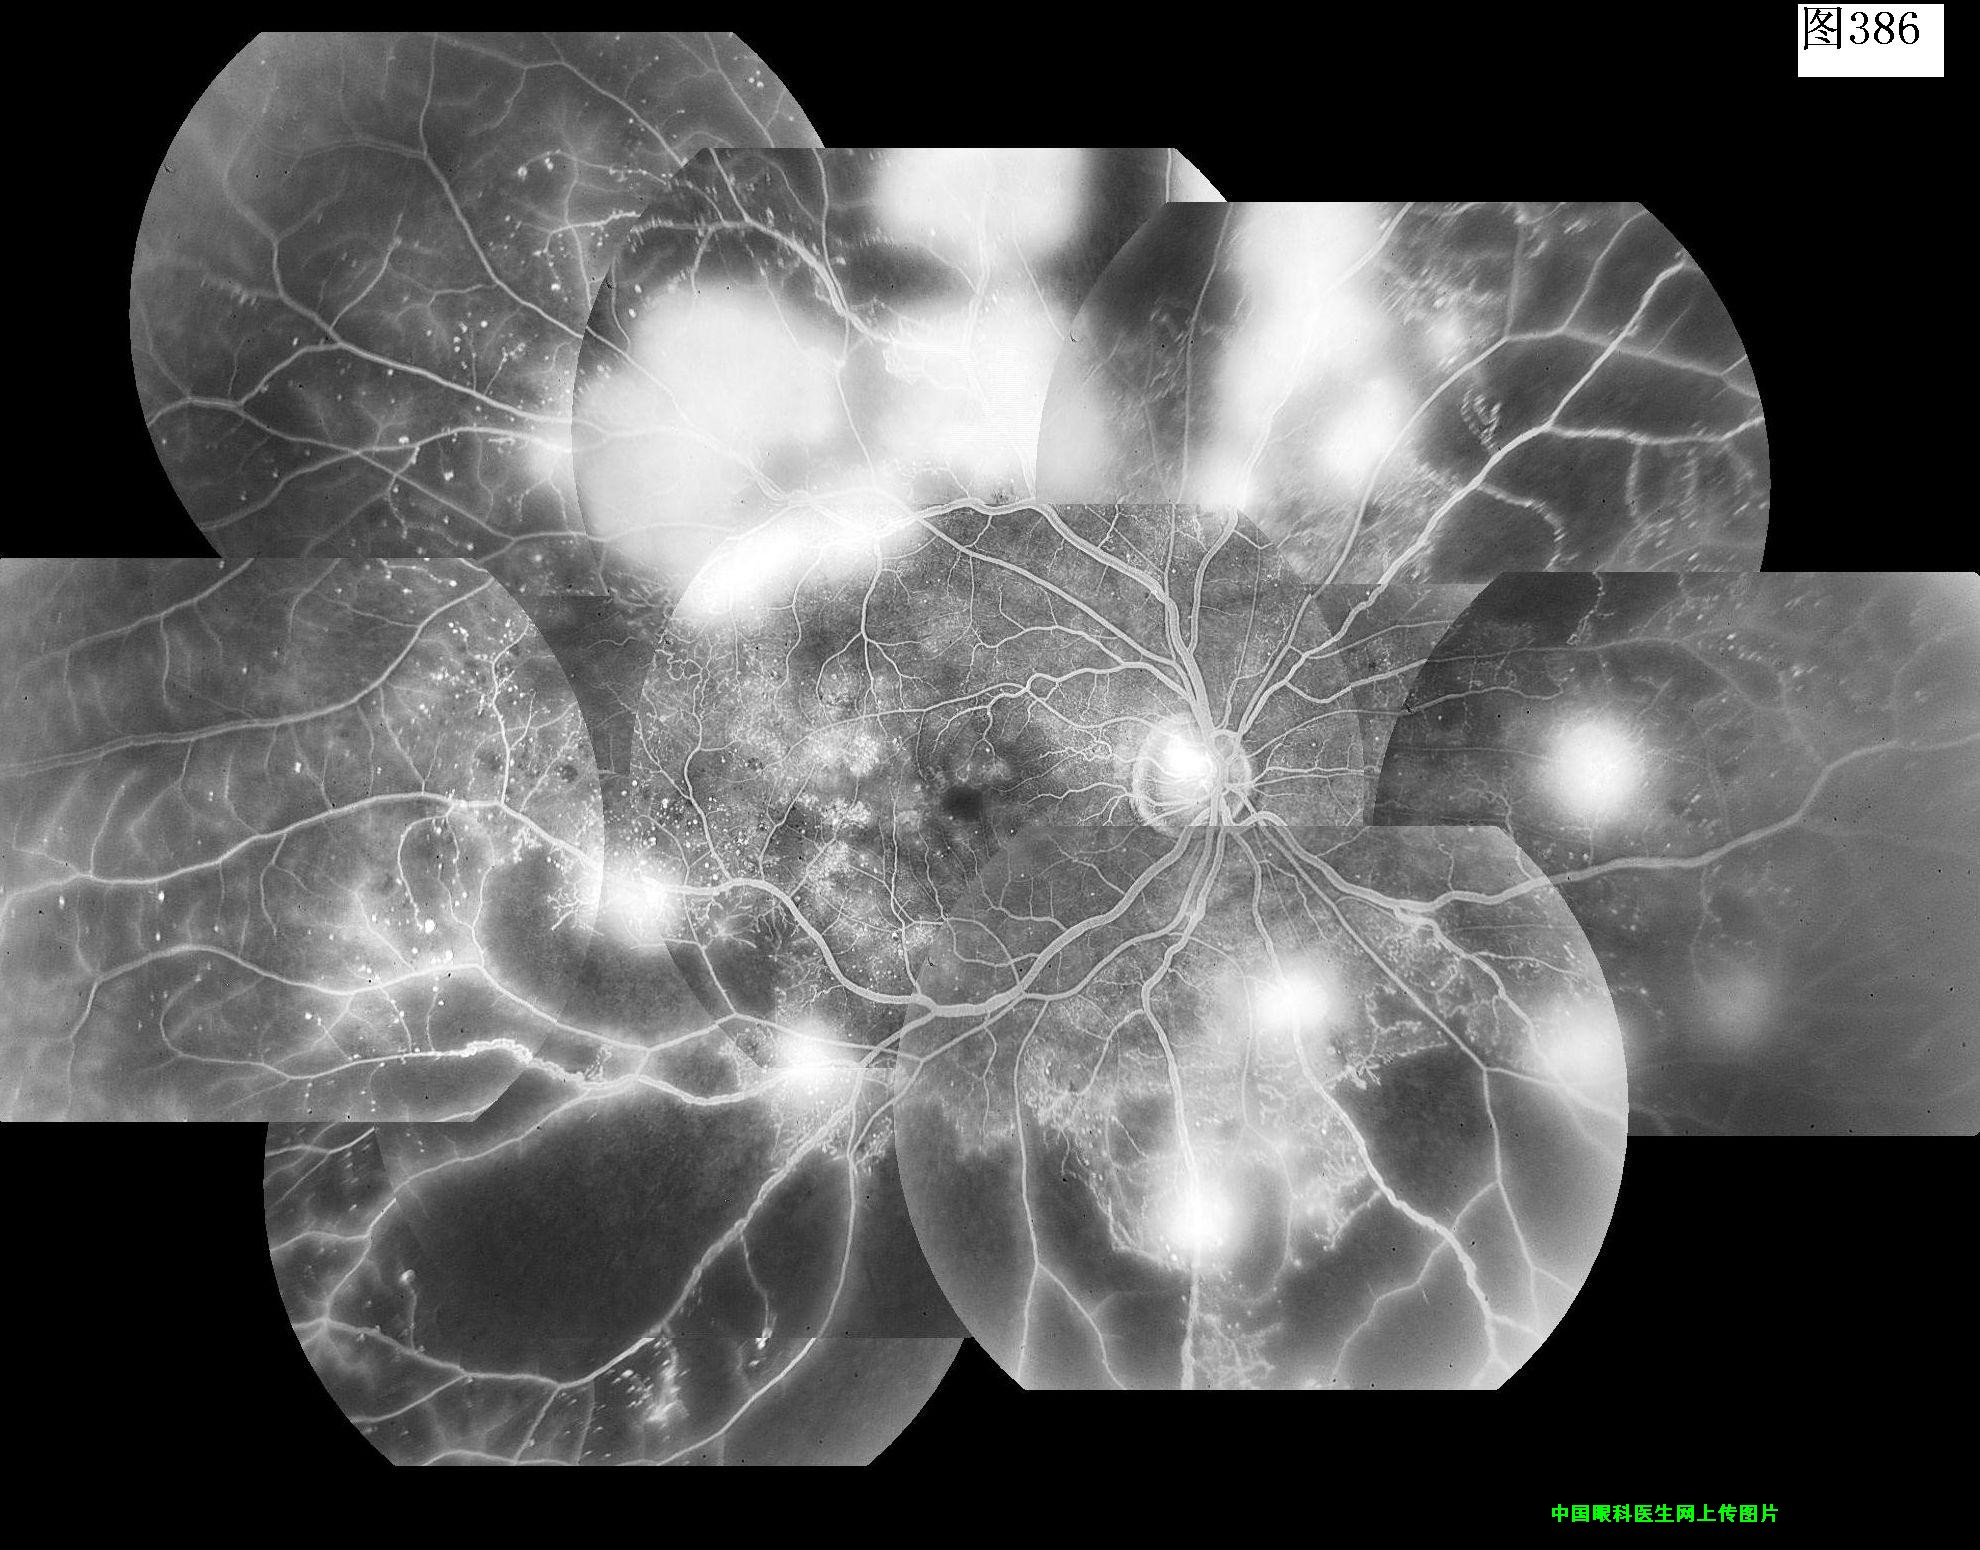

385 386 387 388